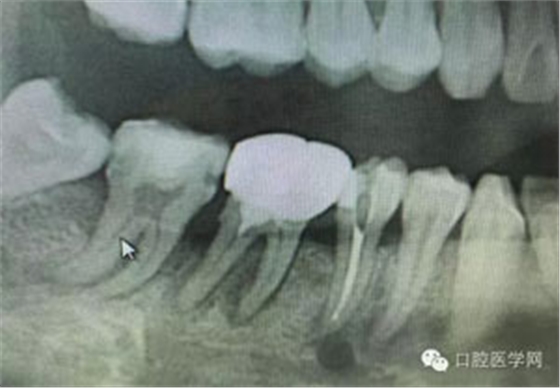

病例1:患者迫切希望保留自己的這一顆牙齒,根尖周陰影比較大,二度松動(dòng).而且旁邊有種植修復(fù)體,和患者溝通好后,治療好后觀察一個(gè)月后冠修復(fù),因?yàn)橛蟹N植的后期修復(fù),所以有了機(jī)會(huì)觀察,術(shù)后三個(gè)月和術(shù)后四個(gè)月,根尖恢復(fù)的還算不錯(cuò),希望能夠繼續(xù)觀察下去.這樣子的病例,做的時(shí)候我們一定要非常的小心,和患者要有充分的溝通以及不同科室的溝通然后決定怎么樣做比較好,假如就是出現(xiàn)了問題,到時(shí)候我們也比較好處理些,免得我們自己到時(shí)候不好收?qǐng)觥?/span> 病例2:364647中齲的樹脂充填,現(xiàn)在樹脂的充填材料非常之多,有些時(shí)候,我們感覺有了好的材料我們就可以做出好的修復(fù),可是這是在我們有扎實(shí)的基本功的基礎(chǔ)上的,我們可以沒有那么好的樹脂,那么多的顏色選擇,修復(fù)的那么的逼真,但是我們至少要恢復(fù)患者牙齒的功能,將腐質(zhì)去除干凈,薄壁弱尖消除掉,選擇好適應(yīng)癥,給患者以盡可能好的修復(fù)。 來源于KQ88